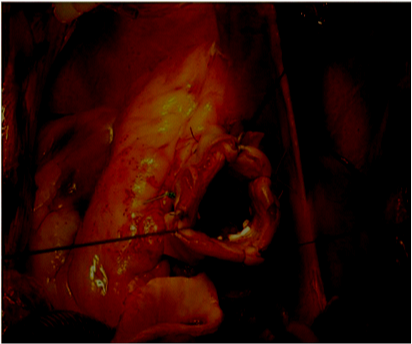

The patient is monitored with TEE. A standard sternotomy is performed. The arterial cannulation site can be the distal ascending aorta or rarely the femoral artery, depending on the extent of the ascending aortic resection. Venous drainage is provided using a single cannula, unless surgical maneuvers are required on the mitral or tricuspid valves. The heart is arrested in diastole using 750cc of integrate cold blood hyperkalemic cardioplegia. Cardiac arrest is maintained during the operation using cold blood retrograde cardioplegia delivered through a coronary sinus catheter. The aorta is transected distal to the sinotubular junction. The right and left coronary arteries are identified for the underlying tissues (Figure 1). Separation of the right ventricular fibers from the left ventricular outflow tract, at the level of the right commissure, is then performed, to allow the placement of the sub annular stitches later in the procedure. Then the aortic valve is inspected, assessing the thickness and coaptation of the leaflets and prolapse of the cusps. If the leaflets appeared morphologically normal, aortic root remodeling is performed. Our technique consists of four steps:

Figure 1 The right and left coronary arteries are identified for the underlying tissues.